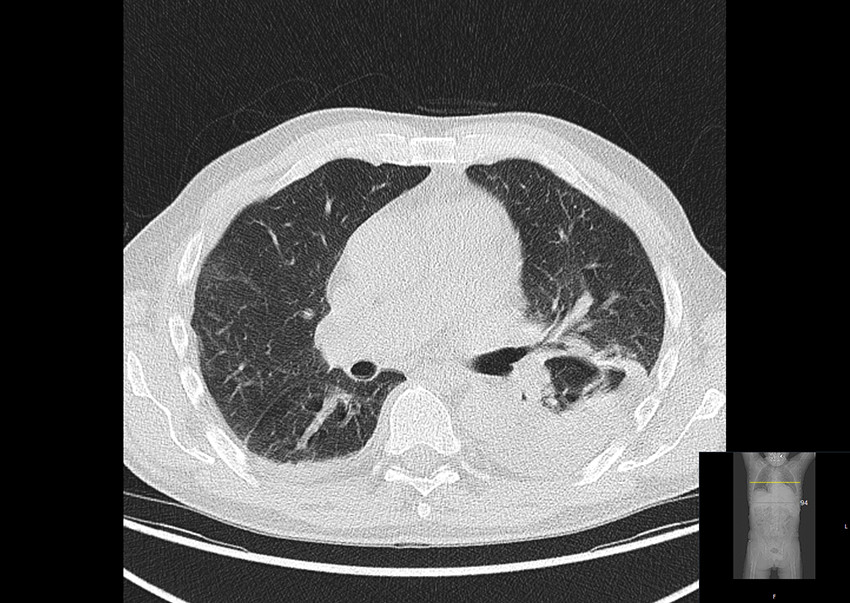

Det var også økt opptak av ¹⁸F-fluordeoksyglukose i benmarg og lymfeknuter, som ble vurdert å være reaktive forandringer. I tillegg ble det funnet et infiltrat i venstre lunges underlapp og pleuravæske (figur 2).

Kjempecellearteritt affiserer personer over 50 år, og årlig insidens i Sør-Norge er beregnet til 16,8 per 100 000 i aldersgruppen ≥ 50 år (4). Lungefortetning er ikke vanlig ved denne sykdommen. Andre årsaker som malignitet og infeksjon kunne ikke forklare funnene i de store blodårene, og ble vurdert som lite sannsynlige. God respons på behandling med prednisolon støttet opp om kjempecellearteritt som diagnose.